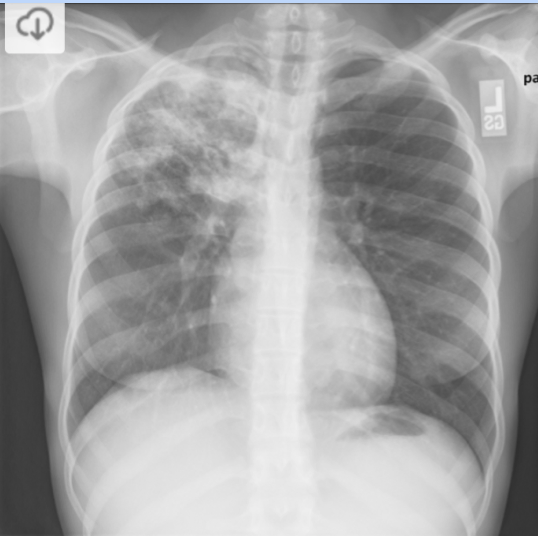

What are expected finding of a patient with TB on a CXR?